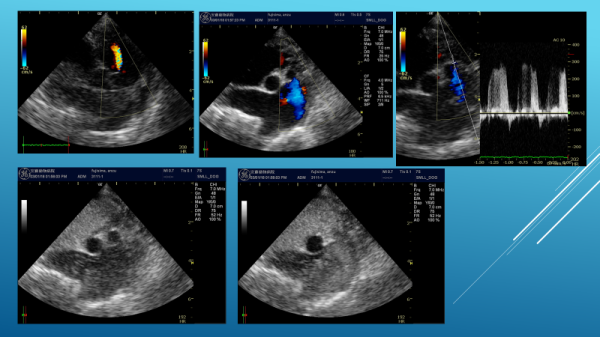

一般身体検査(聴診など)、血液検査、心電図検査、レントゲン検査、心臓エコー検査

エコー心臓・血管造影検査

心臓エコー検査・マイクロバブル造影法